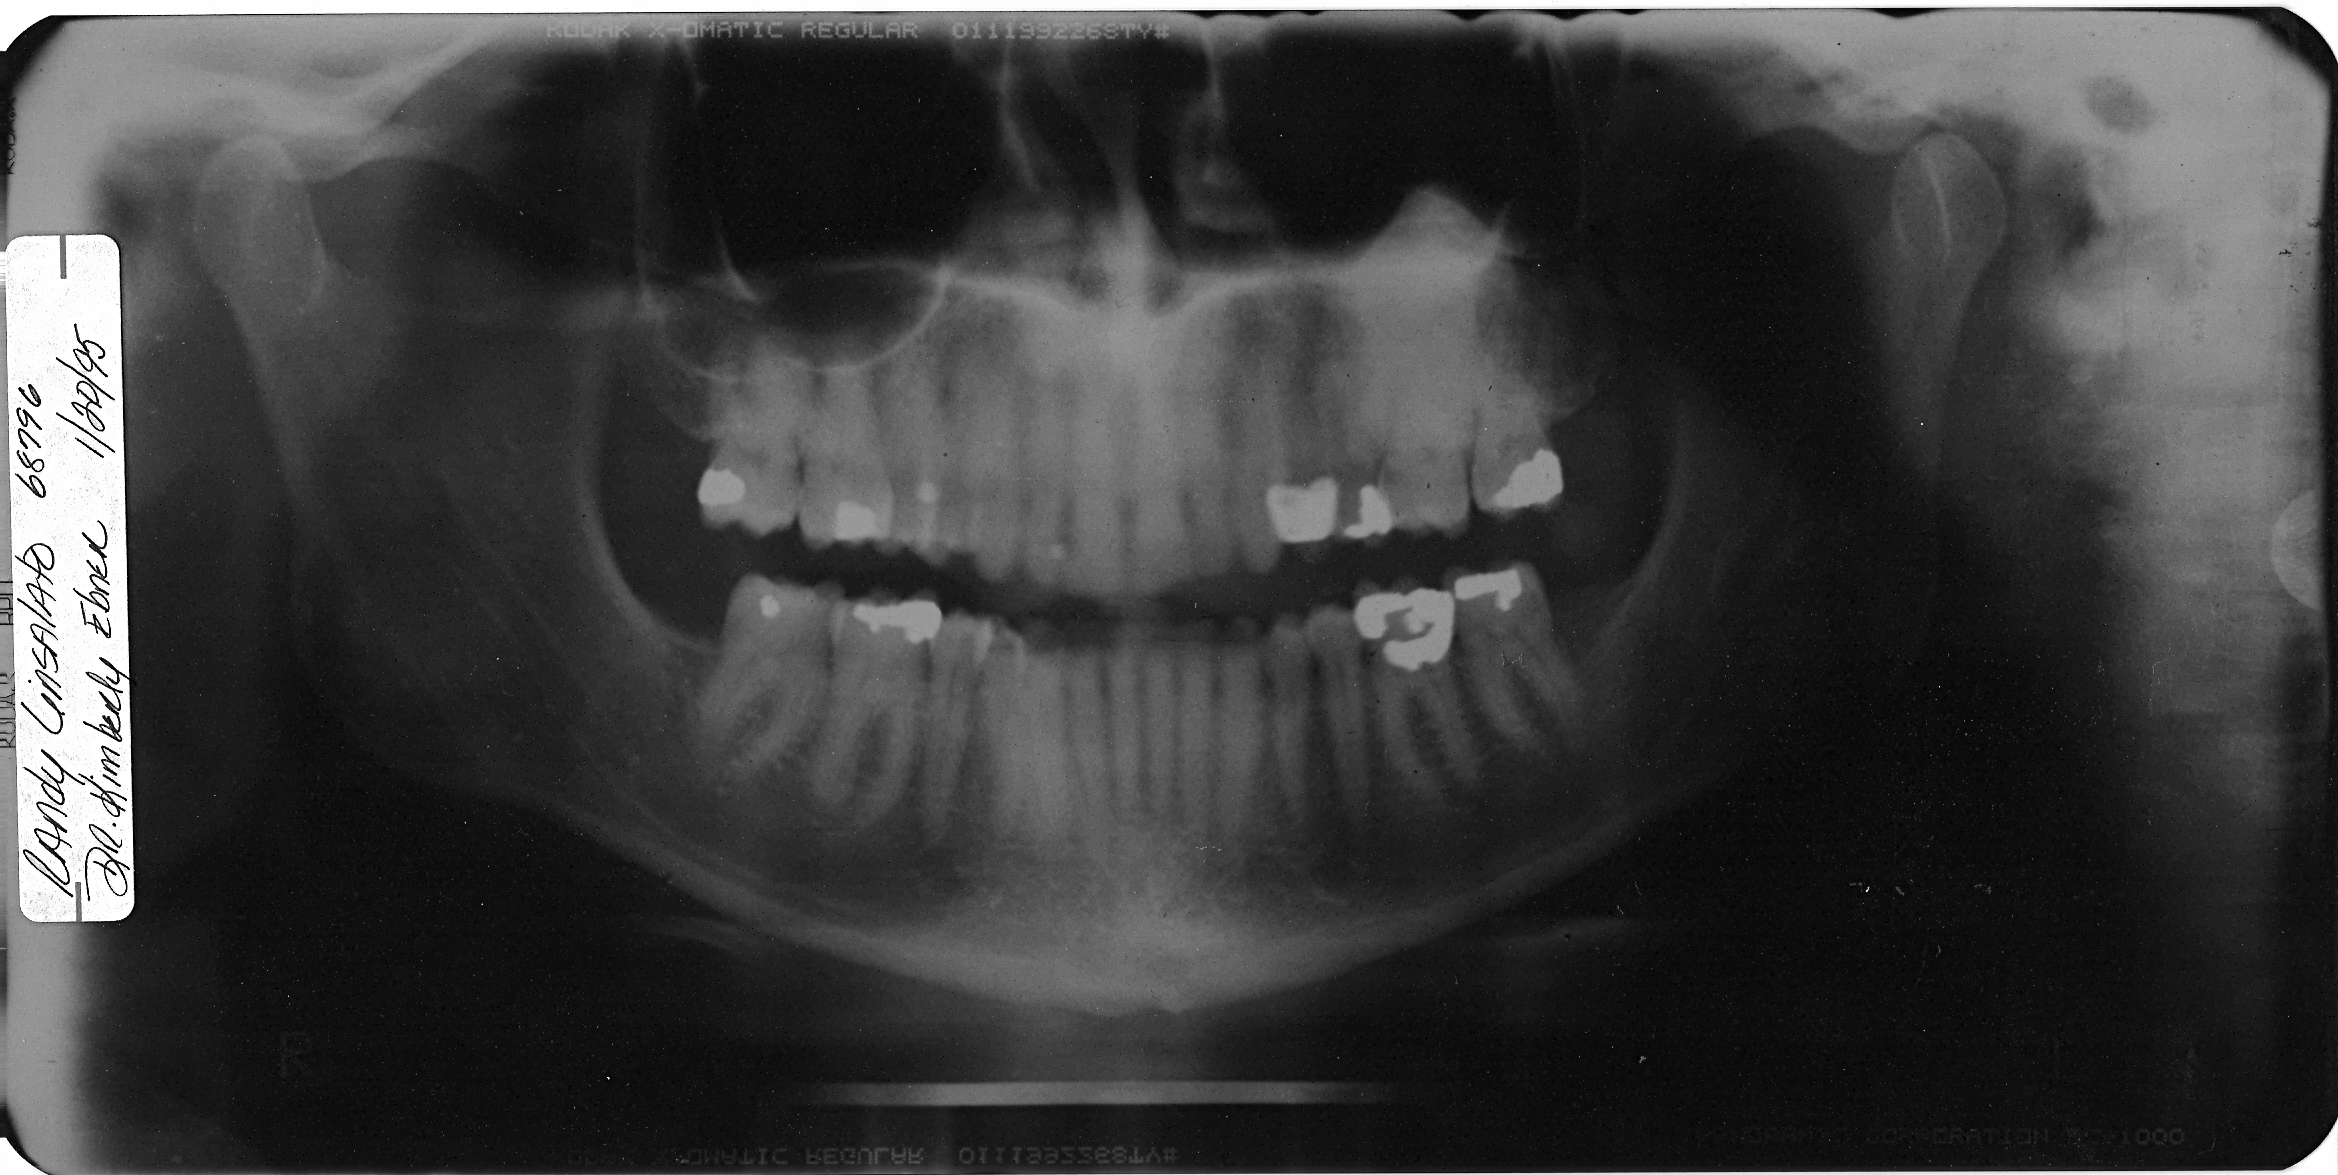

Below are x-rays taken

in 1980 and 1995 which clearly show the bone mass Osteoma involving my

lower sinus and extending down around the roots of teeth 14 and 15

Follow up 15 years later 1995